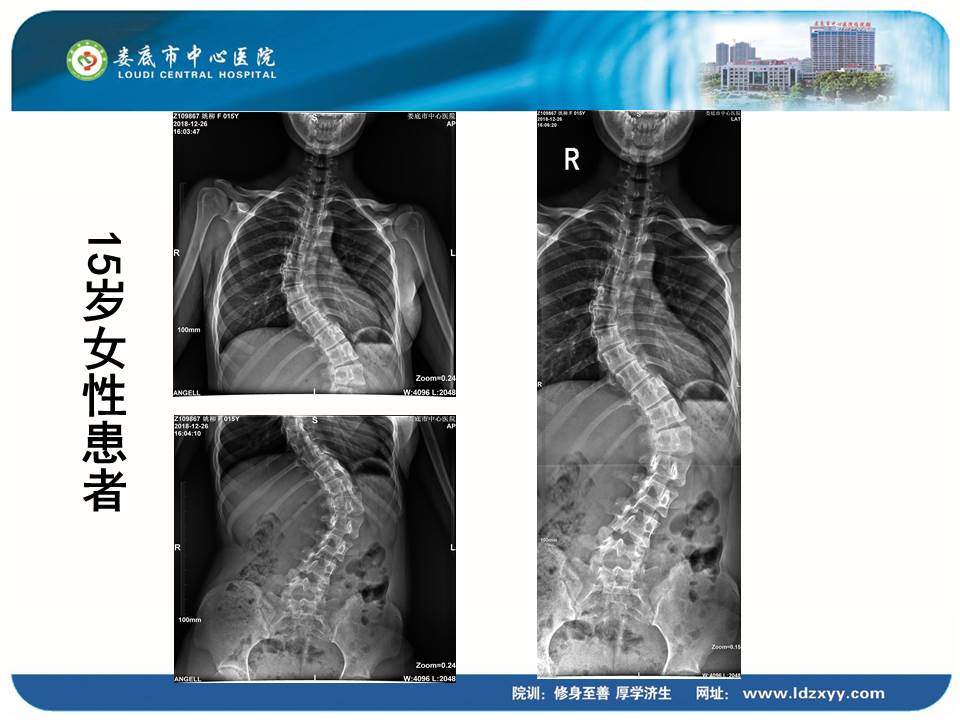

湖南影像學委員、婁底市放射學會副主任委員、婁底市中心醫院放射科劉海潮副主任,則結合動態DR設備的全身拼接應用,分享了動態DR在骨科中的多項應用價值。劉海潮主任認為:由于常規DR的技術限制,長期以來放射科應用傳統拍片并不能有效解決重疊部位的清晰顯影,容易造成漏診誤診,并且受制于成像視野的大小,不能有效顯示脊柱四肢全長的整體結構及病變。而動態DR的17*17英寸大視野成像,配合900多萬的高清像素及可視化的操作,較好地彌補了傳統拍片的不足,而且初步實現了普放向精準診斷方向的轉變劉主任分享了動態DR在全脊柱攝影、全脊柱拼接、脊柱畸形,全下肢X線攝影、全下肢拼接、關節置換中的多項應用,通過站立負重位,快速、便捷攝取 2~3 張原始圖像。在相鄰兩幅原始圖像的重疊部分,對重疊圖像的特征點迅速匹配,進行智能無縫融合處理,將數張有重疊部分的圖像拼成一幅大型的無縫高分辨率圖像。劉海潮主任評價:動態DR通過強大的圖像后處理技術,比如邊緣增強、灰階處理,以及對對比度和銳利度的可調節性,大大提高了拼接影像的質量

全身拼接應用示例